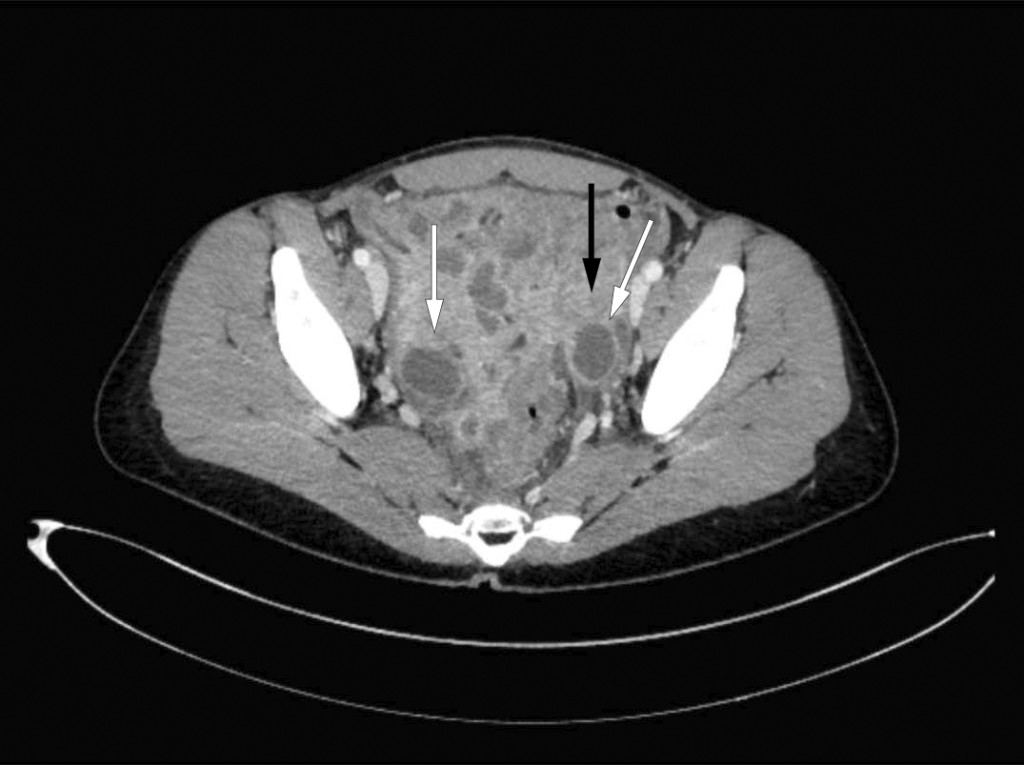

The patient was admitted for the fourth time in four weeks, with increasing abdominal pain, fatigue, signs of infection and organ dysfunction. Twelve months had now passed since the onset of symptoms. She presented with an elevated respiratory rate of 24 breaths/min, a temperature of 38.5 °C, tachycardia of 100 beats/min and blood pressure of 106/64 mm Hg. Examination revealed pronounced palpation and rebound tenderness in the lower abdomen. Blood tests showed leukocytosis 17.9 · 109/L with an excess of neutrophilic granulocytes 15.6 · 109/L (1.7–8.2 · 109/L), a high CRP level of 200 mg/L and elevated biliary parameters with s-ALP (alkaline phosphatase) of 178 U/L (35–105 U/L) and s-GGT (gamma-glutamyltransferase) of 159 U/L (10–45 U/L). Antibiotic treatment with piperacillin and tazobactam was started due to suspicion of an intra-abdominal abscess. A gastroenterologist performed an ultrasound scan of the abdomen, focusing in particular on the intestines and pelvic area, and detected changes in both adnexa and thickening of the wall of the sigmoid colon. A CT scan of the abdomen, which included the lesser pelvis, showed bilateral ovarian abscesses (Figure 1). Blood and urine cultures taken upon admission showed no growth. Serological testing was negative for hepatitis A, B and C, HIV and syphilis. The Quantiferon-TB Gold test for tuberculosis was also negative.

Figure 1 CT scan showed marked inflammation in the pelvis with enlarged, fluid-filled ovaries (white arrows) and thickening…

Figure 1 CT scan showed marked inflammation in the pelvis with enlarged, fluid-filled ovaries (white arrows) and thickening of the wall of the sigmoid colon (black arrow).